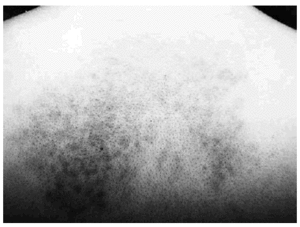

Presentaba una mácula hiperpigmentada de coloración azul-violácea y aspecto moteado que abarcaba la región interescapular. La lesión tenía unos bordes uniformes y bien delimitados (fig. 1). El resto de la exploración dermatológica no ofrecía ninguna otra lesión de interés. Se procedió a la realización de una biopsia cutánea que reveló una epidermis y una dermis normales salvo por la presencia en dermis reticular de células ovaladas, fusiformes y alargadas con intensa pigmentación melánica y algunas ramificaciones (figs. 2 y 3). Se efectuó una tinción con rojo Congo que resultó negativa. Las tinciones inmunohistoquímicas para proteína S100 y HMB 45 demostraron positividad de esas células. En la microscopia electrónica se pudo confirmar la presencia de melanocitos dérmicos. Debido a las dificultades para desparafinar la pieza no fue posible determinar la presencia de vaina extracelular melanocítica debido a la deficiente calidad de las imágenes.

Fig. 1. Mácula hiperpigmentada en región dorsal.